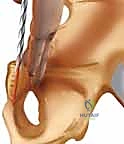

2. الشق الجراحي (Pfannenstiel Incision)

يستخدم الدكتور هطيف غالباً شق "فانينشتيل"، وهو شق عرضي أسفل البطن (يشبه الشق المستخدم في العمليات القيصرية). يتميز هذا الشق بأنه يوفر رؤية ممتازة للمفصل العاني، ويترك ندبة تجميلية مخفية، ويقلل من خطر الفتق الجراحي مقارنة بالشقوق الطولية.

هذه هي المرحلة التي تتجلى فيها خبرة الجراح. يقوم الدكتور هطيف بإبعاد العضلات المستقيمة البطنية بعناية فائقة. يجب حماية المثانة البولية (التي تقع مباشرة خلف المفصل العاني) والأوعية الدموية والأعصاب الحساسة المحيطة. في الذكور، يتم حماية الحبل المنوي، وفي الإناث الرباط المستدير.